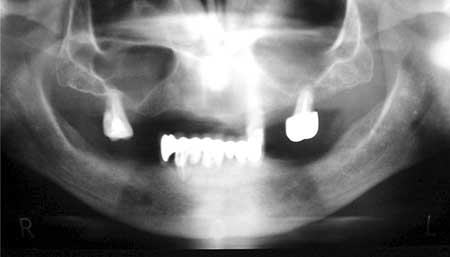

5. Estudio imagenológico: se utilizó la radiografía panorámica (Ver figura 1) donde se evaluó el hueso alveolar (cantidad y calidad), el estado de los dientes remanentes, y fueron descartadas patologías óseas así como también procesos infecciosos. En algunos casos es necesario la toma de tomografías computarizadas asistidos por programas de computadoras para una mejor evaluación del hueso receptor.

Figura 1. Radiografía Inicial

Diagnóstico: Ausencia del 32, 35, 36, 37, 44, 45, 46, 47. Periodontitis crónica generalizada del adulto en 43, 42, 41, 31, 33, 34. La paciente era portadora de prótesis parcial fijas inferiores sostenida por los pilares 43, 42, 41, 31, 33, 34, la cual se encontraba en mal estado, y cuyos pilares presentaban enfermedad periodontal. ( Ver Fig. 1)